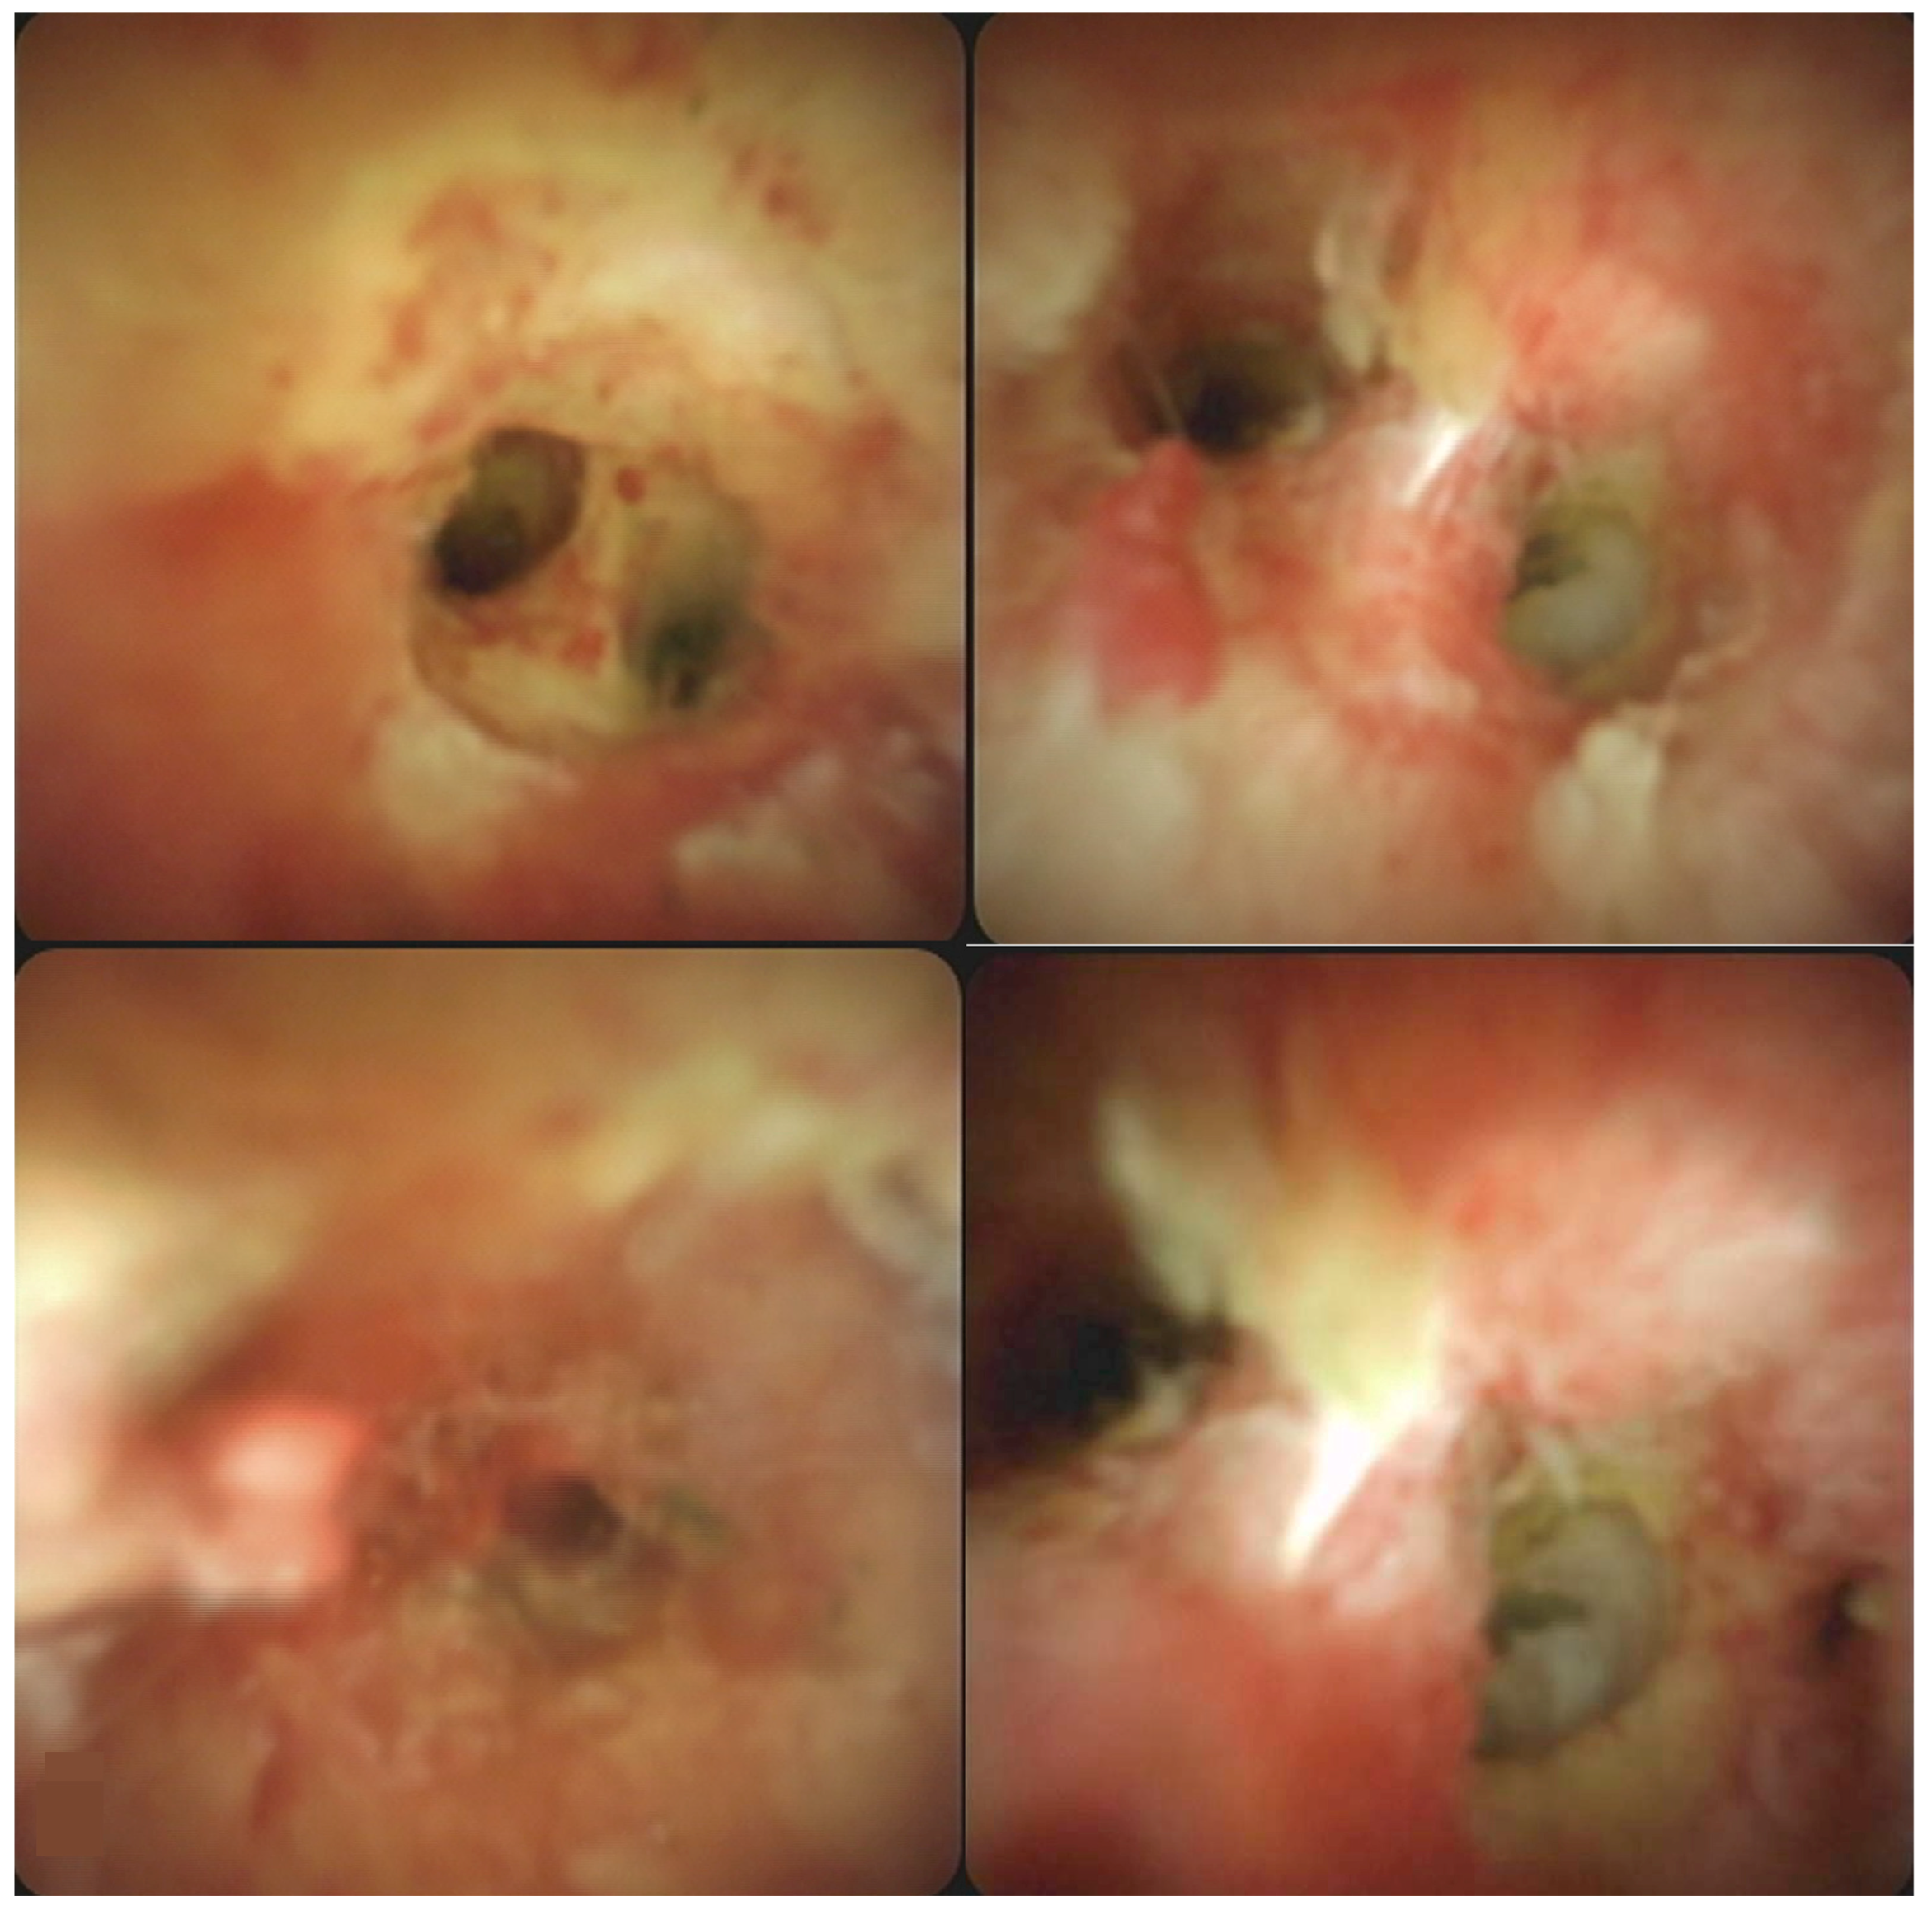

This 59-year-old man suffered from epigastralgia and progressive jaundice for 2 weeks. Tri-phase computer tomography showed diffuse dilatation of intrahepatic ducts (IHDs) with tapering at the hilum (Figure 1). Magnetic Resonance Cholangiopancreatography (MRCP) disclosed diffuse irregular sausage-like IHDs with minimal peri-ductal enhancement and endoscopic retrograde cholangiopancreaticography confirmed a hilar biliary stricture (Figure 2). The SpyGlass™ Direct Visualization System-II (Boston Scientific, Marlborough, MA, USA) demonstrated fibrinous exudates within an ulcerated and erythematous stenotic bile duct. No irregular dilated vessels nor papillary projections were noted, favoring a benign mucosa (Figure 3). POCS-directed biopsy reported chronic inflammation with negative CK AE1/3 staining. Following a 2-month course of ursodeoxycholic acid (15mg/kg/day) for PSC, the patient’s cholestatic-type jaundice normalized. During a three-year follow-up, the patient has been free from recurrent jaundice, cholangitis, and abdominal pain. Notably, both total bilirubin and alkaline phosphatase levels have consistently remained within the normal range, and serial MRCP scans have shown stable results (Figure 4).

Figure 3. Upon cholangioscopic examination, the findings revealed the presence of fibrinous exudates within the confines of an ulcerative stricture, alongside an erythematous stenotic bile duct. Notably, there were no irregular dilated vessels or papillary projections observed, thus favoring a benign chronic inflammatory etiology.